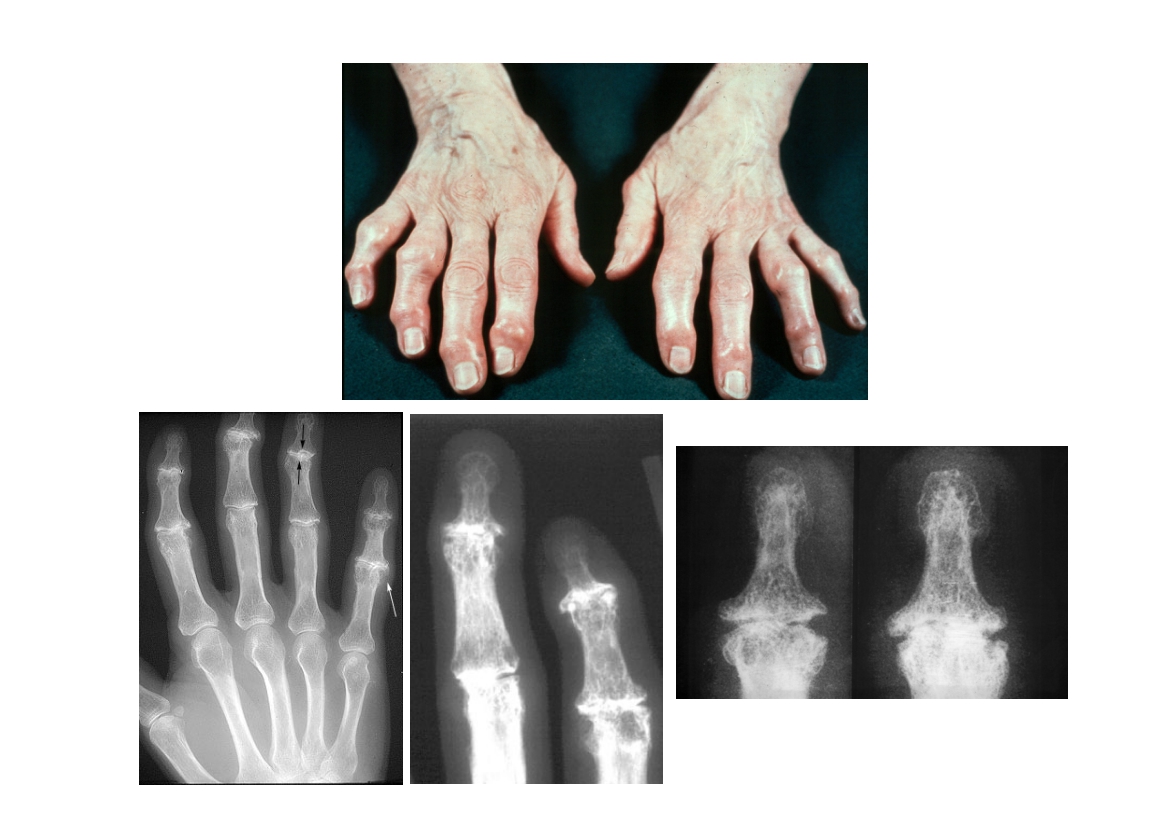

윤정로 병원장님 퇴행성 관절염 치료 자료

윤정로 병원장님의 퇴행성 관절염 치료 관련 자료 입니다.